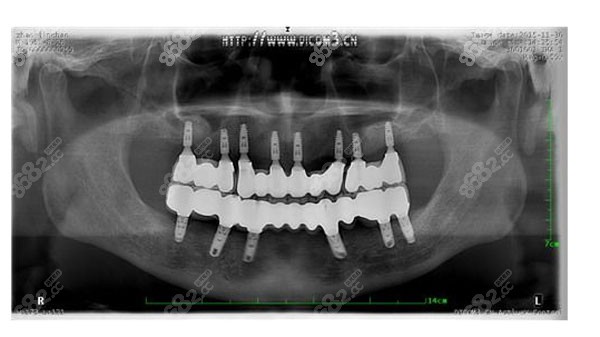

春芽口腔医生集团是国内连锁品牌经营,现在的佛山春芽口腔就是原君美口腔,本院的特色项目就是种植牙!像高难度种植all-on-4,穿颧穿翼种植牙春芽口腔都可以做!每周都会有公办医院的医生定期坐诊,为顾客提供一对一的诊疗服务!

春芽行动发起专为高龄公益种牙专项行动,并成功研发“分分种”、“得力牙”、“德国精密仿生牙”等专为高龄长者“量齿定制”技术,目前已缔造3位百岁老人成功种牙记录,104岁成功种牙,更是刷新了种植牙的高龄记录,备受媒体关注!